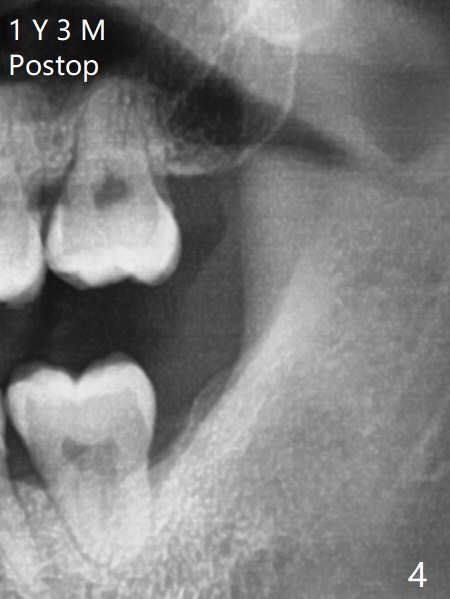

A 19-year-old man with mental retardation returns to clinic for extraction of the 3rd molars in 2 visits (Fig.1,2). The sockets heal without delay (Fig.3,4).